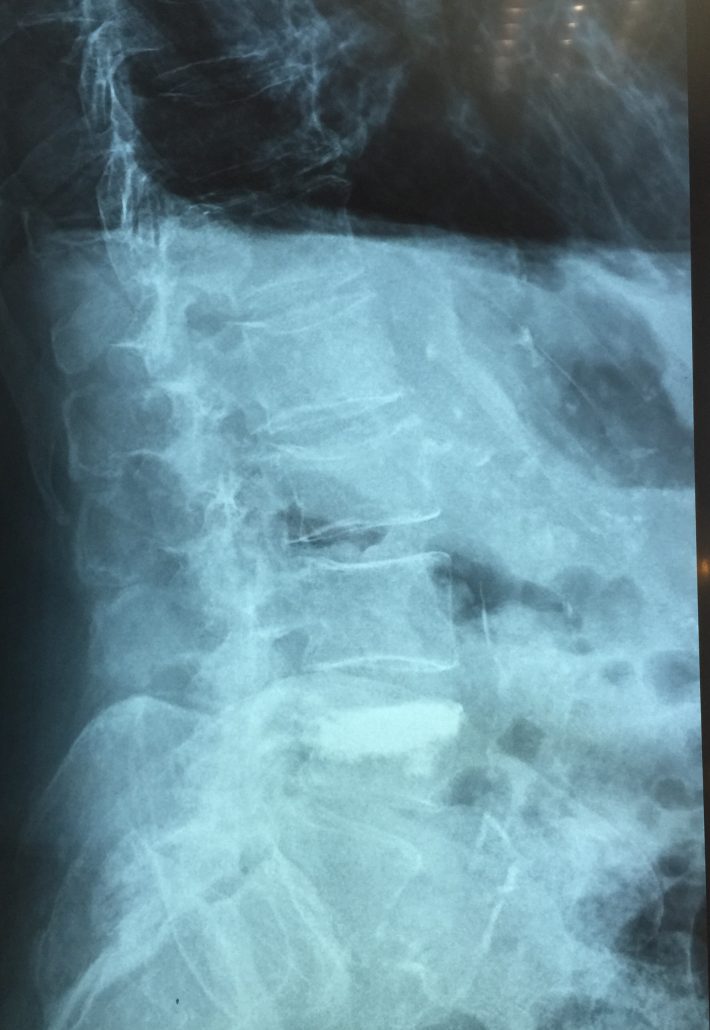

El sistema SpineJack® ha sido diseñado para la reducción anatómica de Fracturas Vertebrales por Compresión (FVC de tipo A1, A2 y A3 según la clasificación de Magerl), con o sin patologías subyacentes que afecten a la calidad del hueso, como la osteoporosis y las lesiones de origen oncológico (metástasis osteolítica o mieloma).

Seguidamente, el médico introduce los implantes e inyecta el cemento óseo que estabilizará la fractura.